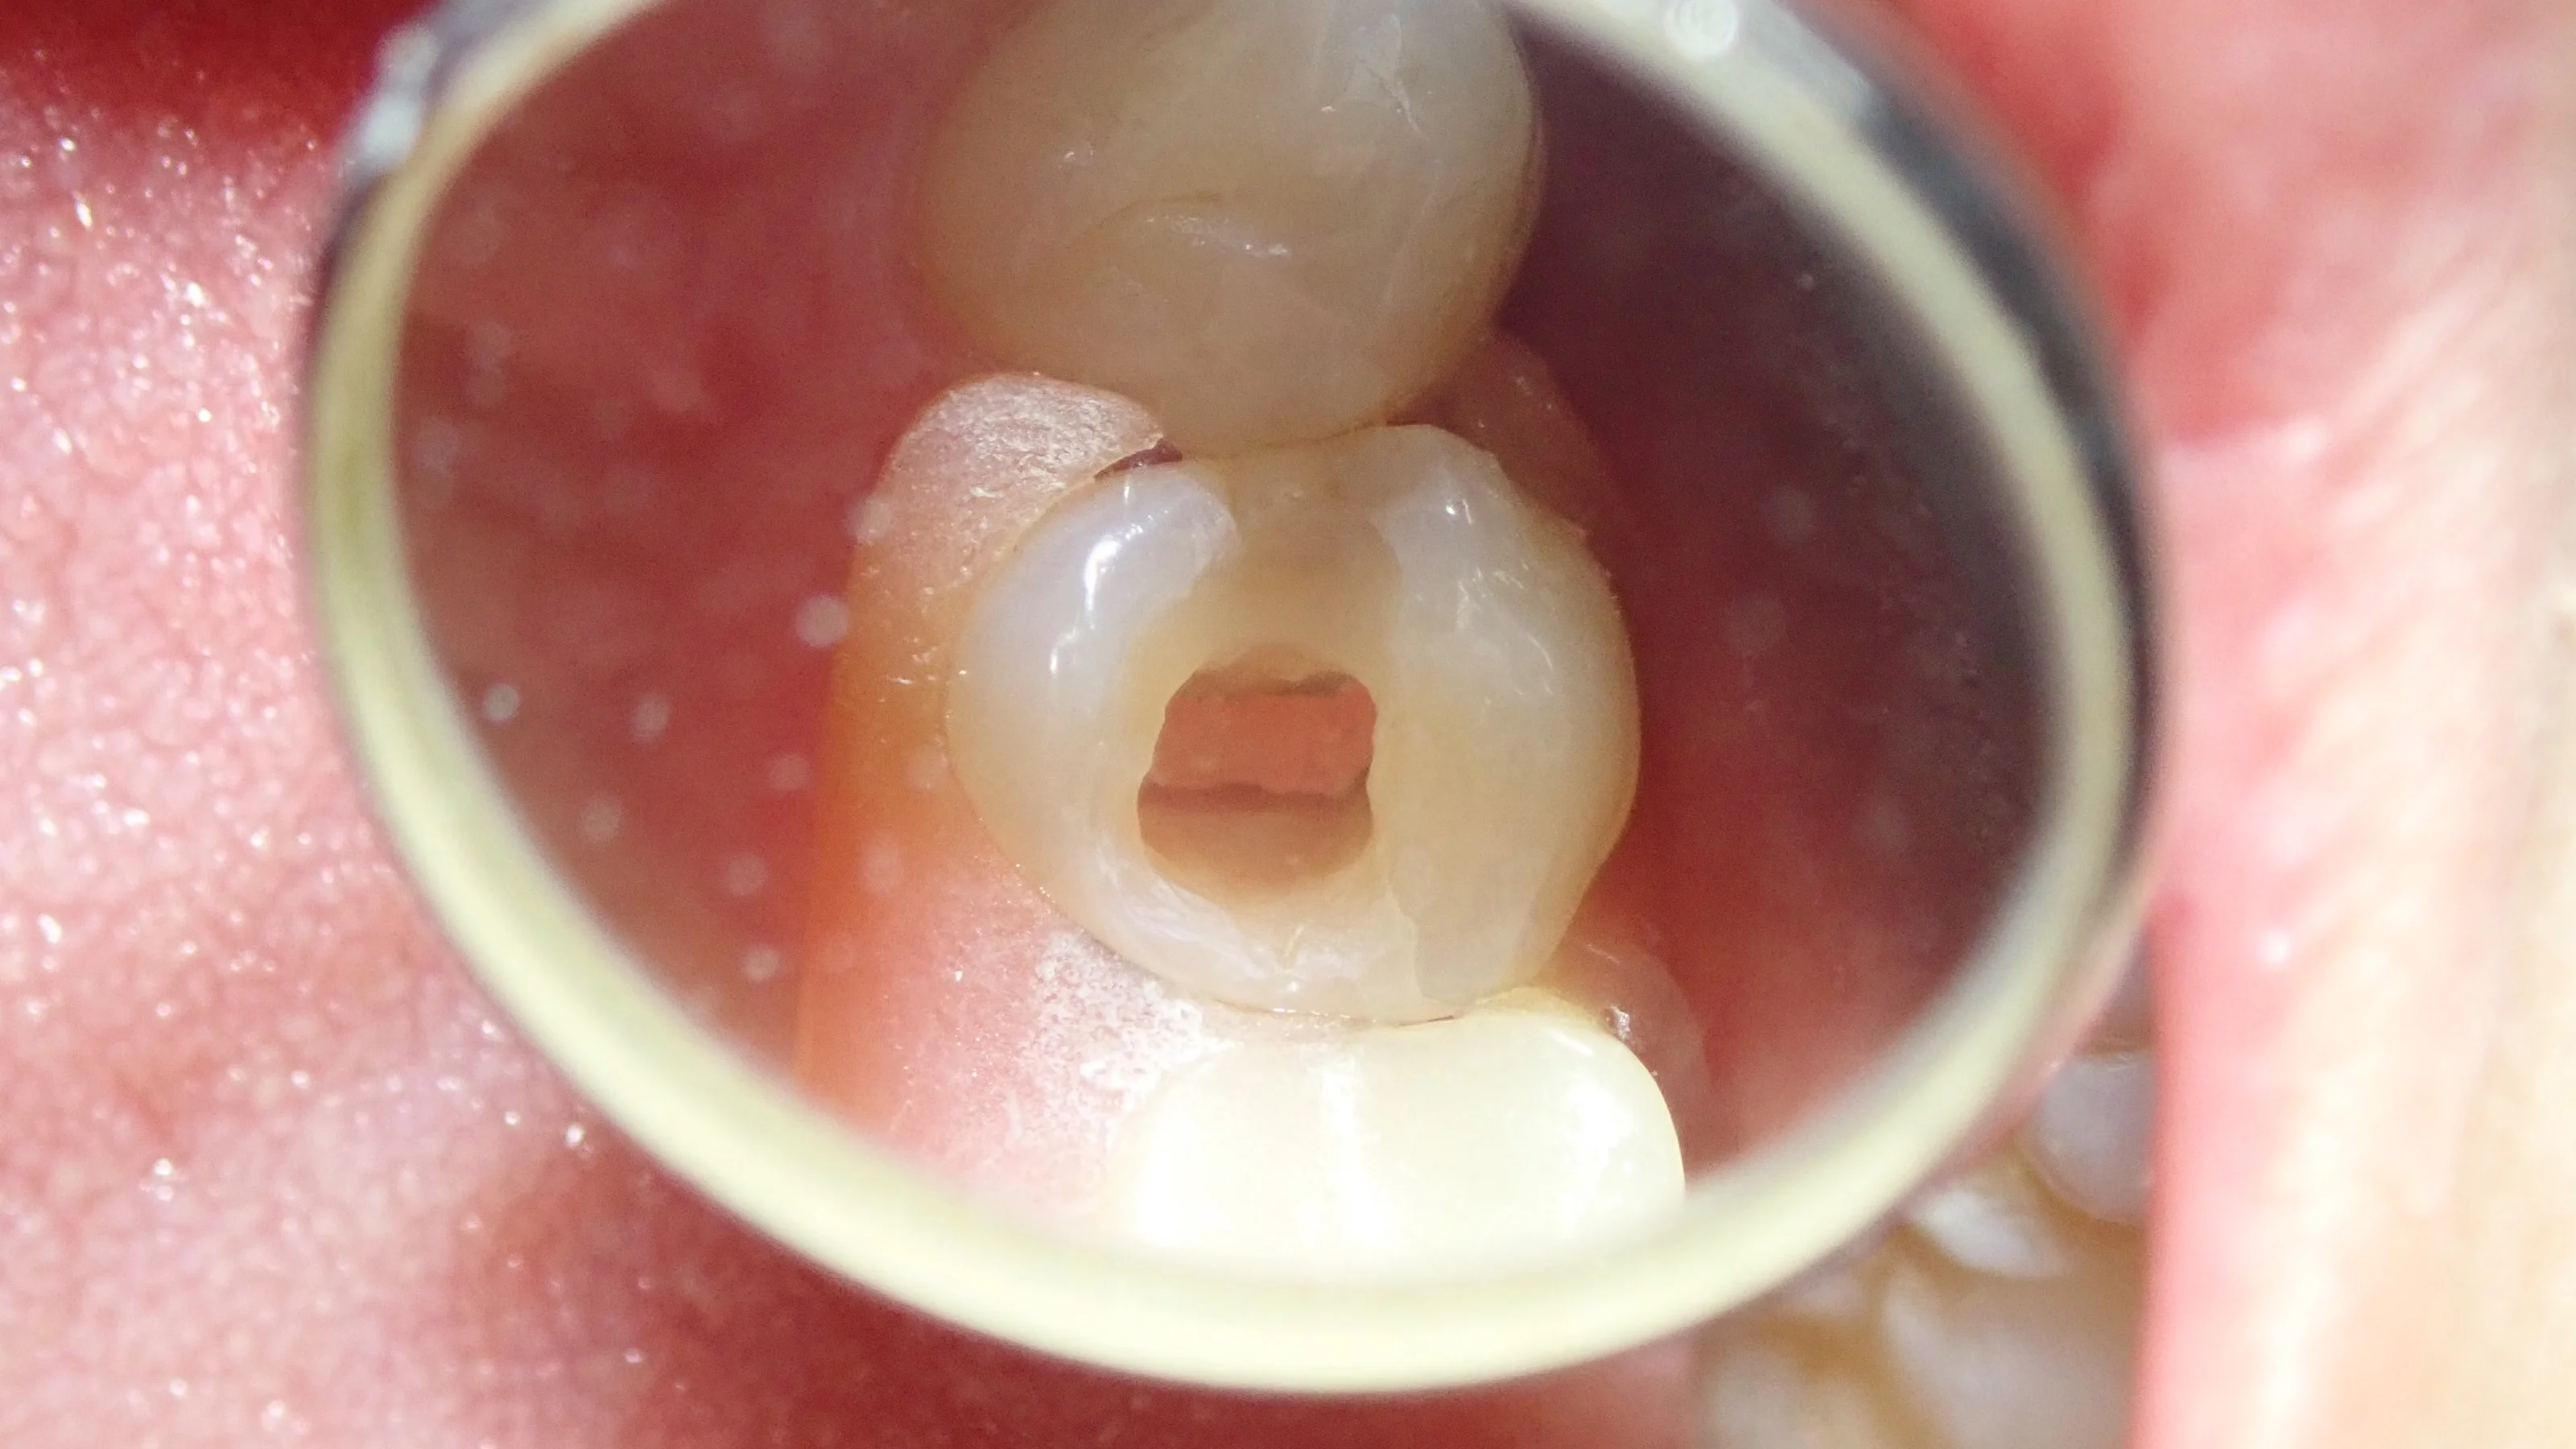

虫歯を取り切った状態がこちら。

・・・案の定、虫歯が神経まで行ってしまっていました。

神経が生きていれば、露出した段階で出血してきますが・・・神経のあるはずの場所を触ってみても全く出血せず。

確実に神経が死んでおり、神経の治療が必要である旨を説明し、同意を得たので、神経の治療へ。

この写真の歯の中央に見えているのが最終的な詰め物です。

ガッタパーチャポイントという柔らかいゴムのようなものを使います。